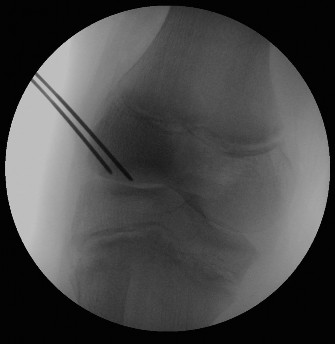

The correct answer is (C). The patient has an OCD lesion of the posterolateral aspect of the medial femoral condyle which is the most common location for these lesions. Pediatric patients have a much better prognosis for OCD lesions as open distal femoral physes are the best predictor of a successful outcome with nonoperative management. Lesions which have synovial fluid behind the lesion on MRI are potentially unstable and require much more aggressive surgical management to prevent detachment and separation. As this patient is young, has open distal femoral physes, and has no instability on MRI, a trial of conservative treatment is appropriate. Arthroscopic drilling (either antegrade or retrograde) can be performed for stable lesions which have not responded to a trial of conservative management (Fig. 10–24). Open reduction and internal fixation should be reserved for unstable lesions.

Figure 10–24